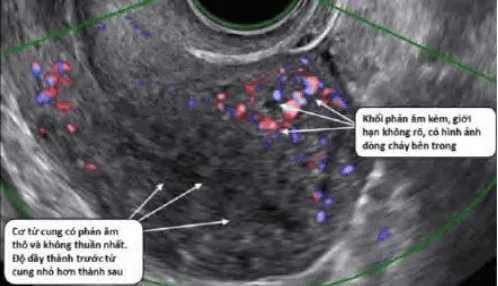

Phần tiêu đề “Cận lâm sàng”Siêu âm thang xám: Khối giảm âm, giới hạn rõ, bóng giảm âm sau.

Hình ảnh “Adenomyosis trên siêu âm”.

Doppler: Mạch ngoại vi u xơ; Phân biệt với polyp (mạch trung tâm) và adenomyosis (mạch nội vi).

Hình ảnh “Adenomyosis trên siêu âm Doppler”.